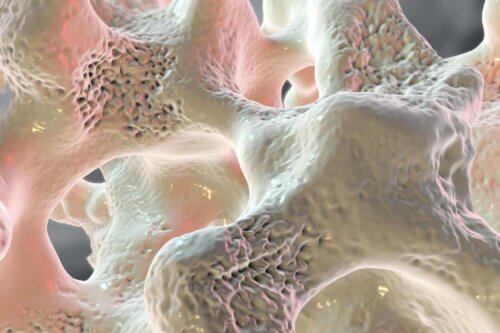

고관절 골절은 생명을 위협할 수도 있는 심각한 부상으로 골다공증 같은 합병증까지 발생할 수 있다. 안타깝게도 주로 노령층의 건강에 악영향을 미치는데 스페인 같은 국가에서는 고관절 골절 환자가 매년 6만 명씩 발생하여 천 명 중 한 명꼴로 고생한다고 한다.

골다공증은 고관절 골절을 위험 요소로 노년 여성은 특히 더 주의해야 한다.

앞서 이야기했듯이 고관절 골절 환자는 80대 이상이 대부분이며 주로 여성 환자가 많다. 골다공증이 잘 걸리는 80대 이상은 작은 충격과 압박에도 뼈가 쉽게 부러질 수 있다.

뼈는 세포로만 완벽히 붙지 않는다. 개인의 성장과 생리적 요구에 따라 손상됐던 뼈가 유합되는 과정을 골 재생성이라고 한다. 골조직 손상률이 생성률을 앞서는 30대 이후부터는 뼈가 약해지고 다공성으로 변화한다.

골다공증이 있는 노령층은 젊은 사람보다 고관절이 부러질 확률이 훨씬 높다. 넘어지면서 대퇴부가 파열되고 그 영향으로 골절 부상까지 입게 된다.

- 골다공증: 골다공증은 낙상으로 고관절 골절이 발생할 확률을 높인다